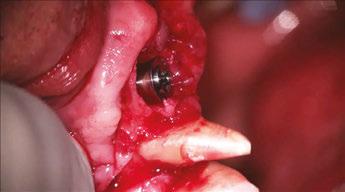

Building on the basics

Let’s review a recent case that showcases the rationale and techniques of the top three. It is common to utilize several suturing techniques in surgical closure, especially in larger grafting cases. In the following case, a lateral sinus lift was performed, and all three techniques were used to their full effect. Simple interrupted sutures are used to close small incisions and place tissue margins accurately back in place; horizontal mattress sutures are used to hold membranes in place and relieve tension over the incision line, and running interlocking continuous sutures are used to close longer incisions with watertight closure for maximum healing potential via primary closure.

A patient presented with a failing bridge on the upper left that is supported by three mini implants. The implants directly perforate the sinus and only ~2mm of residual bone height remains on the crest (Figure 8). The mini implants were removed, and a

Figures 7A and 7B: Horizontal mattress sutures are useful for helping to secure membranes in grafting situations and relieving tension in longer span incisions Figures 8A and 8B: The pre-op condition of the patient with mini implants engaging minimal bone and perforating the sinus. The patient’s implant supported bridge was loose and causing discomfort Figure 9: A periosteal biting mattress engages only the periosteum in the buccal vestibule and exit and re-enters on the lingual tissue, helping to secure the membrane tightly over the window and crest